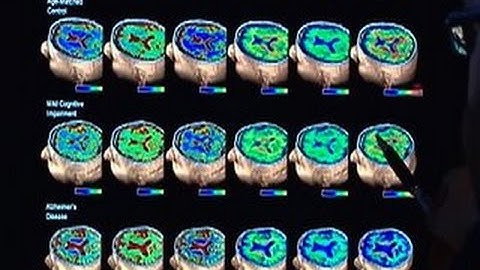

Researchers find protein linked to memory loss